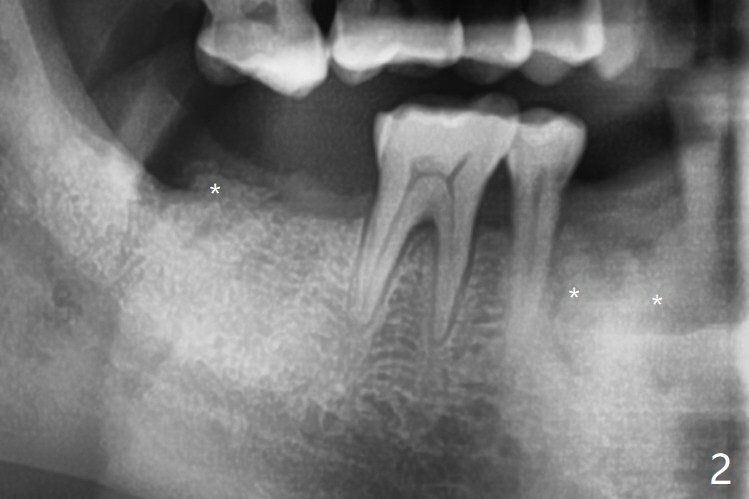

拔除32号牙时发现它接近31区(将要植牙),必须植骨(近中部分(远中塞入胶原塞)),27,28颊侧骨板缺失(大量肉芽组织),植骨理所应当,而且必须拼命推压,但愿推到颊侧骨板,细的皮质骨没有压制感,非要加入粗的松质骨皮质骨,一张12x12毫米胎盘膜剪成两片覆盖27/28和32拔牙窝,4-0 PGA缝线固定,拍摄术后半侧全景片后(图二 (*:骨粉)),使用牙周敷料保护伤口。27/28重叠,近远中8.11毫米,可以植入一个植体,做悬臂桥,或者植入两者之间。The bone graft remains in place 1 month postop (Fig.8).  术后一个月27,28号牙位骨粉保持原位(图八)。